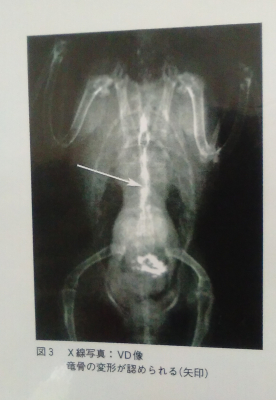

X線検査:

肺炎・気嚢炎→異常なし

心臓・肝臓→異常なし

VD像(仰向けのレントゲン)で竜骨が変形している様子がみられる。

第36病日(再診):とくに記載するような異常はなくなった。X線検査で甲状腺は初診時より縮小しているが、まだ正常な大きさまでは縮んでいないため、同じ内服薬を28日間投与

第64病日(再診):とくに記載するような異常はなくなった。X線検査で甲状腺は縮小してX線写真上では確認できない。